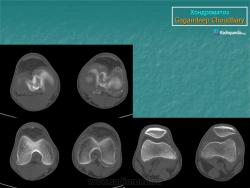

Хондроматоз внутрисуставной (синовиальный).

Приложения:

1.sin_.slayd80.jpg2.sin_.slayd81.jpg3.sin_.slayd82.jpg4.sin_.slayd83.jpg5.sin_.slayd84.jpg6.sin_.slayd85.jpg